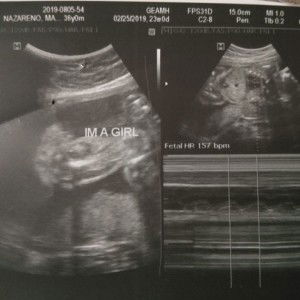

Got a bun in the oven